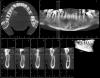

pakulino Опубликовано 8 октября, 2013 Поделиться Опубликовано 8 октября, 2013 Уважаемые коллеги пацыентка 32 года. Пришла поправить прикус сняли панорамку потом томографию ситуацыя не из легких что посоветуете? Ссылка на комментарий

Sahan Опубликовано 8 октября, 2013 Поделиться Опубликовано 8 октября, 2013 17,28,38,47,48 на вынос. Со всем остальным можно работать. Чистка, вектор, открытый кюретаж с GBR плюс Эмдогейн. Далее ,через пару месяцев повторная оценка и составление окончательного плана лечения. Лечение будет недешевым, без 100% гарантий, требующим постоянной поддерживающей терапии иначе все станет еще хуже чем до начала лечения. Однако шансы продлить жизнь зубам хорошие. 2 Ссылка на комментарий

Sahan Опубликовано 9 октября, 2013 Поделиться Опубликовано 9 октября, 2013 Что мы сможем оценить, кроме гигиены, через пару месяцев?Нужно ли как то разгружать от чрезмерной нагрузки оставшиеся зубы? Каппы или съёмный протез?И как Вы поступаете с пациентами которые не улучшают гигиену?, меняется ли план лечения или Вы просто отказываете в дальнейшей работе? И еще вопрос, не подскажете как наши европейские коллеги взаимодействуют с ортодонтами в таких случаях?Да и кстати я заметил что с таким пародонтитом чаще всего пациенты с юга, у меня по крайней мере чаще всего. Через пару месяцев кроме гигиены мы оцениваем состояние пародонта, перспективность каждого зуба. Выбираем вариант реабилитации( необходимость : коронок, имплантатов, ортодонтии). В такой работе разгружать оставшиеся зубы обязательно, причем я бы в первую очередь предложил имплантаты, а во вторую сьемный протез. Если перед началом лечения пациент подписался под обязательствами и не выполняет их, то дальнейшее лечение либо заканчивается и проводится только поддерживающая терапия, либо пациент возвращается на правильный путь, либо кардинально меняется план лечения и пац либо соглашается на него либо уходит в свободное плавание.В Европе очень плотно сотрудичают парадонтологи с ортодонтами. Кстати вовремя курса в Исландии так же проходил всеевропейский конгресс ортодонтов и у нас был целый день посвященный ортодонтии. Кстати в представленном кейсе я бы ортодонтически дистализировал 3.7. По остальным зубам нужно модели смотреть. Ссылка на комментарий